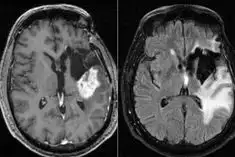

4. 진단은 MRI, CT 스캔을 통해 이루어지며, 조직 검사로 확진합니다.

교모세포종의 진단은 주로 고해상도의 영상 진단 도구인 MRI 또는 CT를 통해 이루어집니다.

이러한 검사를 통해 종양의 위치, 크기 및 주변 조직과의 관계를 정확히 평가할 수 있습니다.

또한, 최종적인 진단을 위해서는 조직 검사가 필수적으로 수행됩니다.